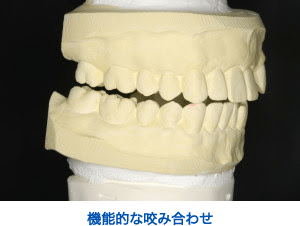

当院では『咬み合わせ』を非常に重要視しております。

特に矯正治療後の咬み合わせは、とても大切です。

矯正治療を行うということは、その人の咬み合わせを全て変えてしまうということです。

当院では『ミューチュアリー プロテクテッド オクルージョン』を採用しております。

これは、前歯と犬歯と奥歯がそれぞれを守り合いながら、長期的に機能するという考え方です。

そのためには、歯の形態と歯並びが非常に重要になります。